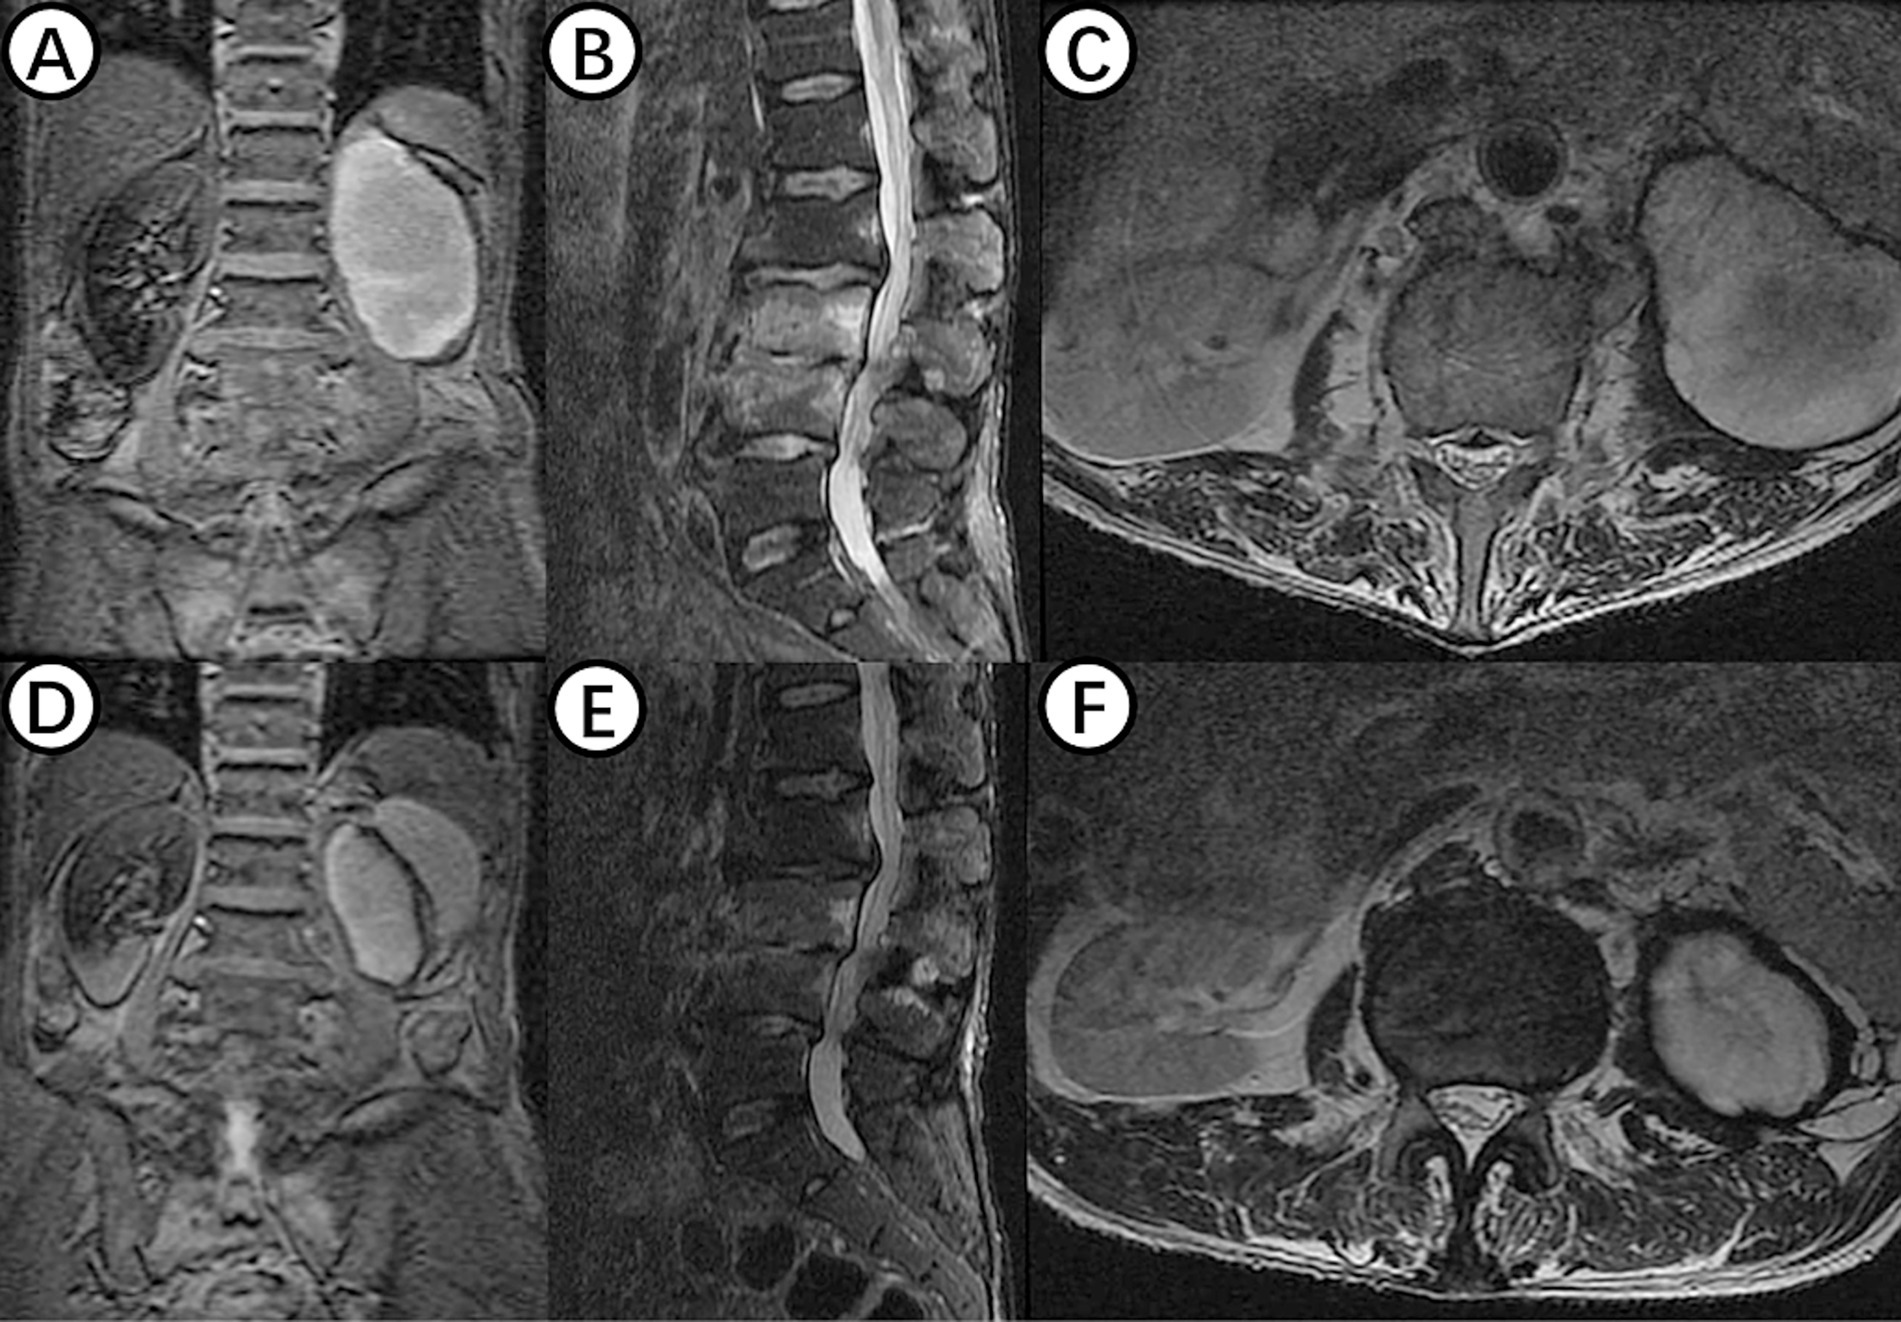

Figure 1

(A) Shows the surgical position for changing NPWT. (B) Displays intraoperative C-arm fluoroscopy positioning. (C,E) Present preoperative MRI scans showing high signal in the L3 and L4 vertebral bodies and intervertebral space, as well as abscess in the intervertebral space, bilateral lumbar muscles, and paraspinal muscles. (D,F) Demonstrate postoperative MRI showing decreased inflammation and edema signals in the L3 and L4 vertebral bodies and intervertebral space, with negative pressure sponge and drainage tube in place. (G) Depicts the NPWT sponge inside the body being replaced.

On July 28, 2023, the patient underwent the second minimally invasive lateral approach lumbar spine lesion clearance surgery. Approximately 355 mL of fluid was drained postoperatively for 7 days. Prior to the surgery, a follow-up MRI was performed, which showed significant improvement at the site of the lesion (Figures 1D,F). On August 4, 2023, the patient underwent the third minimally invasive lateral approach lumbar spine lesion clearance surgery. During the surgery, necrotic tissue was scraped from the intervertebral space, the wound was thoroughly cleaned, and a NPWT negative pressure drainage was replaced (Figure 1G). On the third day after surgery, the patient’s blood pressure was 80/55 mmHg, and blood tests showed a hemoglobin level of 52 g/L, an activated partial thromboplastin time (Activated Partial Thromboplastin Time) of 39.3 s, and a Thrombin Time (TT) of 22.2 s (The changes in coagulation indicators are detailed in Figure 2). The drainage volume reached 500 mL of bloody fluid in 24 h, indicating hypovolemic shock. Emergency exploration on August 7, 2023, revealed arterial blood oozing from the L3/4 intervertebral space with poor clotting. The coagulation parameters on the same day suggested that the patient was in a peak state of hypocoagulability (see Figure 2). The wound was irrigated with saline, electrocoagulated to stop the bleeding, and packed with gelatin sponge and hemostatic gauze. The wound was satisfactorily closed with a negative pressure drainage tube left in place. The patient received 4 units of red blood cells on the day of surgery. On the first postoperative day, the patient’s albumin level was 27.2 g/L, and hemoglobin level was 48 g/L. The patient received concentrated red blood cells (AB type), fresh frozen plasma (AB type), and cryoprecipitate, as well as furosemide injection and a saline solution with dexamethasone. The patient received 4 units of red blood cells, 600 mL of fresh frozen plasma, and 10 units of cryoprecipitate on the first postoperative day. On the second postoperative day, the hemoglobin level was 60 g/L, and the patient received 2 units of red blood cells, 610 mL of fresh frozen plasma, and 10 units of cryoprecipitate. On the third postoperative day, the blood pressure was 126/87 mmHg, the hemoglobin level was 87 g/L, and the albumin level was 37.7 g/L. The patient was given two units of red blood cells, resulting in a significant improvement in their anemia symptoms. Refer to Figure 3 for a detailed treatment process. MRI review indicates the presence of a hematoma in the surgical area (Figures 4A–C). After four effective debridement surgeries and antibiotic treatment, the lumbar spine infection improved gradually, and the retroperitoneal hematoma was absorbed. Follow-up abdominal MRI scan after 3 months showed an encapsulated fluid signal in the retroperitoneum (Figures 4D–F).

(A–C) Shows MRI examination of the lumbar spine in a patient with hemorrhagic shock, revealing an oval-shaped fluid signal at the lower pole of the left kidney, likely due to hematoma at the surgical site. (D–F) Displays findings from an MRI examination 3 months postoperatively, showing significant reduction of the hematoma signal, with disappearance of inflammatory signals in the L3 and L4 vertebral bodies and intervertebral space.